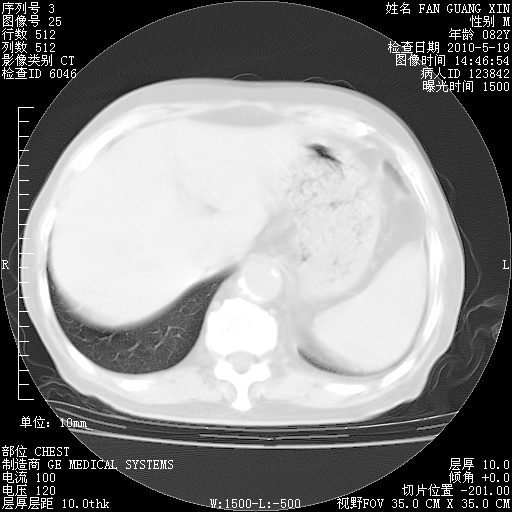

治疗3周后的肺部CT

治疗3周后的肺部CT纵隔窗